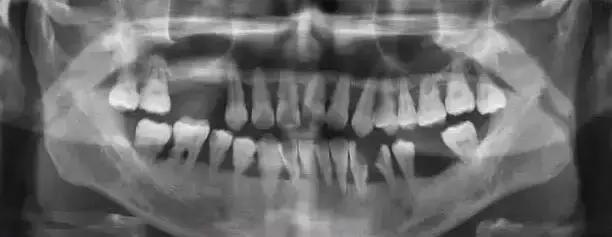

2.牙石 牙石是指沉积在牙面上的矿化的菌斑,根据其沉积部位和性质分为龈上牙石和龈下牙石两种。

(1).龈上牙石:位于龈缘以上的牙面上,肉眼可直接看到。在牙颈部沉积较多,特别是在大涎腺导管开口相对处,如上颌磨牙的颊侧和下颌前牙的舌侧沉积更多。龈上牙石中无机盐的主要来源是唾液中的钙、磷等矿物盐。

(2).龈下牙石:位于龈缘以下、龈袋或牙周袋内的根面上,肉眼不能直视,必须用探针探查,方能知其沉积部位和沉积量。龈下牙石中无机盐的主要来源是龈沟液。 牙石对牙周组织的危害,主要是构成了菌斑附着和细菌滋生的良好环境。